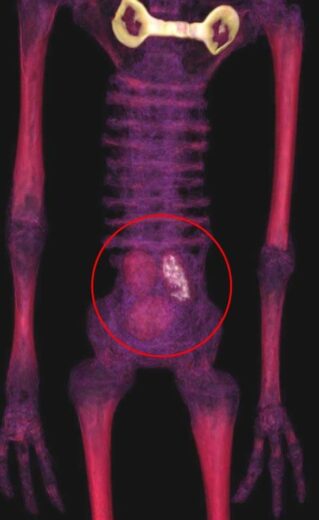

«Últimas imágenes tomográficas del interior de los huevos ubicados en el vientre de “Josefina” confirman la presencia de material orgánico en formación (posible embrión), lo que demostraría que estos cuerpos desecados son en realidad entidades biológicas que en algún momento tuvieron vida» manifiestan.

«Además, en la parte superior de la toma del tronco completo de Josefina se observa la misteriosa placa de metal incrustada en su pecho. Que Nasca la Verdad» finalizan».